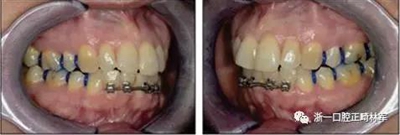

由于下頜中切牙間沒有間隙行下頜正中切開術,故進行術前正畸擴展間隙。下頜前牙粘托槽,中切牙托槽成交放置,將中切牙牙根分開。使用0.018X0.018鎳鈦絲及置于下頜左、右中切牙之間的推簧推間隙。3個月后拍攝CBCT示已有足夠間隙行下頜正中截骨術。

手術前三周,上、下頜磨牙和前磨牙使用分壓圈進行分牙。術前一天,去除下頜切牙托槽,安裝hyrax擴弓器。